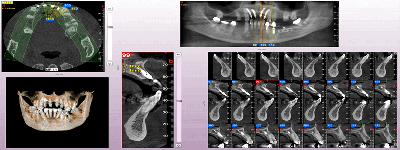

Proactive Dental Management thru our 3D Imaging Manipulation Software

With Oral Maxillofacial CT Scans, your dentist enhances his ability to proactively manage your health concern thru accurate diagnosis & better treatment planning. Moreover, the patient benefits from a painless,low radiation dose CT Scan procedure.